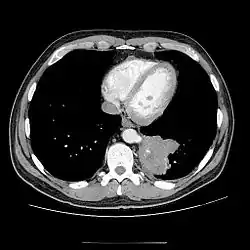

Wada przebiegająca bezobjawowo, bez połączenia z oskrzelem, może być wykryta przypadkowo na zdjęciu przeglądowym klatki piersiowej jako okrągława masa o wysyceniu typowym dla tkanek miękkich, najczęściej zlokalizowana nad przeponą w dolno-tylnej części lewego płuca. Obraz radiologiczny objawowej sekwestracji płucnej naśladuje zmiany torbielowate, jamiste lub marskie. Aortografia pozwala ocenić zaopatrzenie zmiany w naczynia tętnicze.